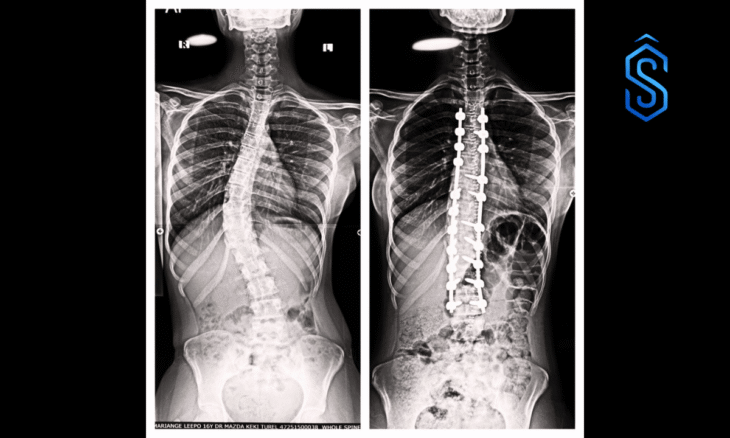

Mumbai: A life-changing surgery at Wockhardt Hospitals, Mumbai Central, helped a 16-year-old girl overcome severe scoliosis, a spinal deformity that causes the spine to curve abnormally.

The young patient arrived at Wockhardt Hospitals struggling with both physical pain and emotional distress. Her spine was curved from the chest to the lower back, involving 12 vertebrae – nearly her entire spinal column.

Under the expertise of Dr Mazda Turel, Consultant Brain and Spine Surgeon, the hospital performed a complex corrective spinal surgery. Surgeons placed precision-guided screws and rods to realign each vertebra, gradually straightening the spine and restoring the body’s natural balance.